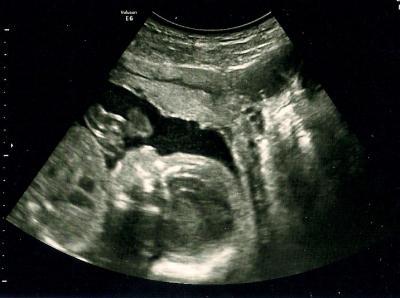

2. Bild

Bild zu